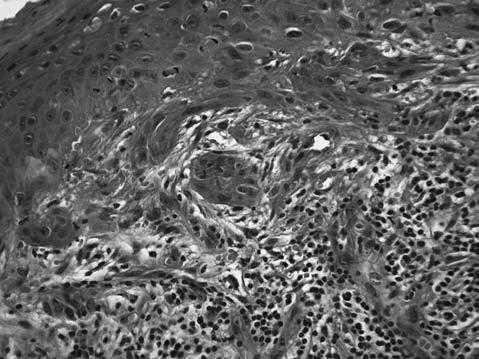

En marzo de 2000, se realizó resección local. Histología: “fístula branquial con foco de carcinoma escamoso en su interior” (fig. 1). Presentó recurrencia local a los 6 meses.

Fig. 1. Histología (hematoxilina-eosina). Se observa foco localizado de carcinoma escamoso maduro en medio de tejido típico correspondiente a quiste branquial. Agradecemos la imagen al Dr. Julio San Martino.